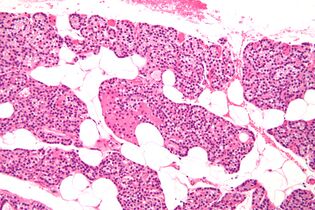

Microanatomy

The parathyroid glands are named for their proximity to the thyroid—and serve a completely different role than the thyroid gland. The parathyroid glands are quite easily recognizable from the thyroid as they have densely packed cells, in contrast with the follicular structure of the thyroid.[6] Two unique types of cells are present in the parathyroid gland:

• Chief cells, which synthesize and release parathyroid hormone. These cells are small, and appear dark when loaded with parathyroid hormone, and clear when the hormone has been secreted, or in their resting state.[7]

• Oxyphil cells, which are lighter in appearance and increase in number with age,[7] have an unknown function.[8]